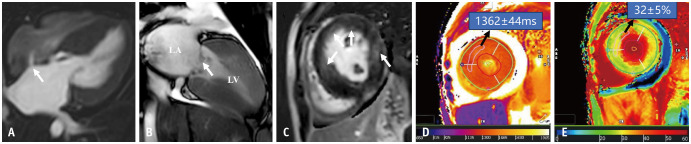

Cardiac MRI Characteristics of Noonan Syndrome Associated With Hypertrophic Cardiomyopathy and Congenital Heart Disease.

与肥厚性心肌病和先天性心脏病相关的Noonan综合征的心脏MRI特征